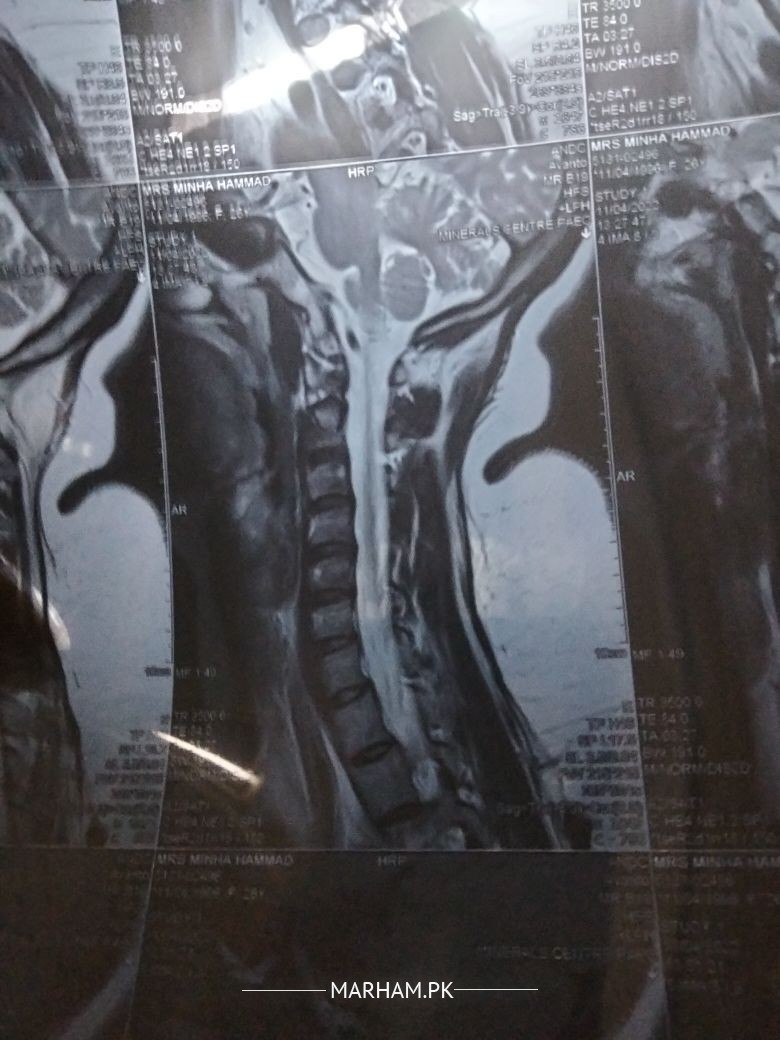

mujhy neck pain hy physiotherapy krwaty tu aram mil jta duragesic or gabica 50 lay rhy aram nhy ata .. koi mustakil solution Nazar nhy ata methcobal bi Khai 6 month injections bi piye ab derd back mn agai plz koi btaye achi medican lacolep xiga rapid bi kha chuki exercise bi krty bht derd hty lifestyle bi mutasir hta Allah apka hamyunasir hu

there's issue on your MRI spine

Kya issue hy MRI spine mn